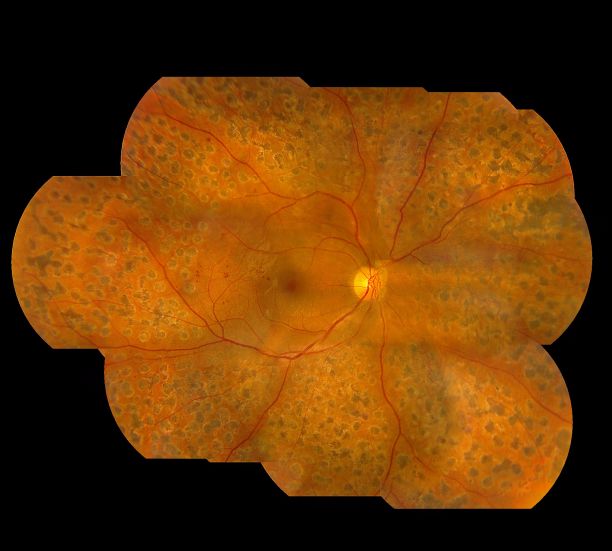

其實(shí),糖尿病性視網(wǎng)膜病變是一種常見(jiàn)的眼科疾病,一般糖尿病患者血糖沒(méi)有控制好,就可能影響到眼睛,進(jìn)而導(dǎo)致視網(wǎng)膜發(fā)生病變。

而我們的視網(wǎng)膜布滿了大量的微絲血管,如果血糖長(zhǎng)期不穩(wěn)定,有可能導(dǎo)致視網(wǎng)膜血管內(nèi)皮細(xì)胞遭到破壞,進(jìn)而引發(fā)一系列的眼底病變,如微血管瘤、糖尿黃斑水腫、視網(wǎng)膜新生血管,甚至視網(wǎng)膜脫落或青光眼,這些眼疾若未及時(shí)治療,嚴(yán)重情況下有失明的危險(xiǎn)。